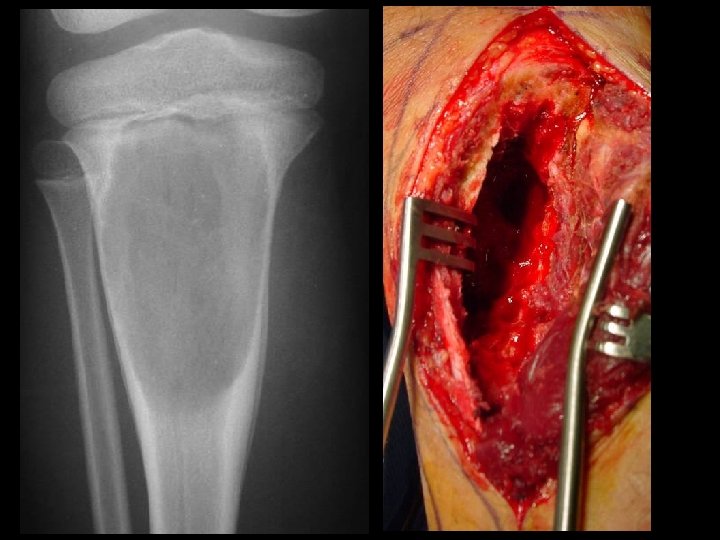

A 14 year old boy presents with pain and a mass above the knee. Take a look at the AP and lateral radiographs first.

Biopsy obvious superficial mass, blind biopsy • tissue compartments must not be • contaminated Biopsy should be done in consultation with a – tumor surgeon. skinny needle most helpful with metastatic • disease core best for primary tumor •

Cross-sectional imaging Pictures are pretty, but diagnosis • established at histology MRI best for most tumors • optimal results at sites with experience – Role of CT limited • may assist in assessing tumor matrix – useful in directing biopsy –